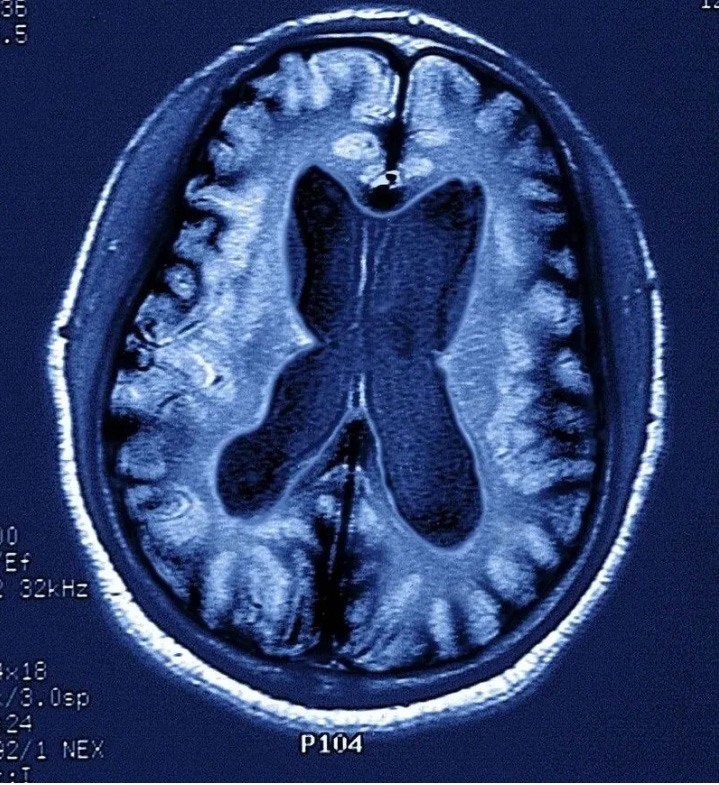

一般來說,記憶力下降是失智癥的核心癥狀,但它不是診斷失智癥的充分條件,目前臨床上診斷失智癥還要結合其它手段,如一系列的量表評估,MRI等客觀檢查。

因而當記憶出現問題時,可就診于各大醫院神經內科記憶門診,完成一系列的神經心理學量表測試、抽血檢查(查APOE ε基因型等)、腰穿腦脊液檢查(Aβ1-42的檢測)、尿和便標本、普通頭顱核磁,如有必要還需做PET-MRI以檢測腦內淀粉樣蛋白沉積。通過上述的綜合測試評估病情,給予診療意見。